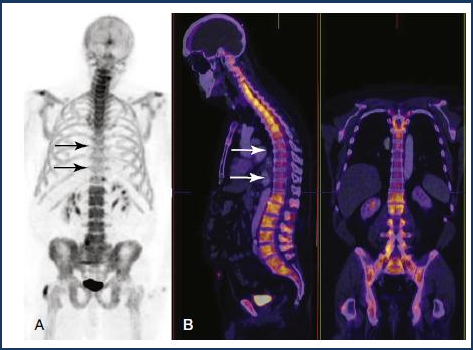

Bone scan

Principles, Indications, and Examples

Principles and indications

Detection, staging and follow-up of bone metastasis

Evaluation of bone pain in patient with normal plain radiograph (unexplained bone pain) Radiotracer: 99mTc-MDP (methylene diphosphonate)

Pathophysiology

Chemisorption to the hydroxyapatite crystal

Increased uptake

Increased blood flow

Increased osteoid formation

Increased mineralization of osteoid

Interrupted sympathetic nerve supply